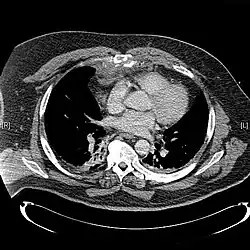

As radiografias do tórax são realizadas em pessoas com trauma torácico e sintomas de fraturas do esterno, e podem ser seguidas por tomografia computadorizada.[13] Como as radiografias tiradas de frente podem não detectar a lesão, elas também são tiradas de lado.[14]